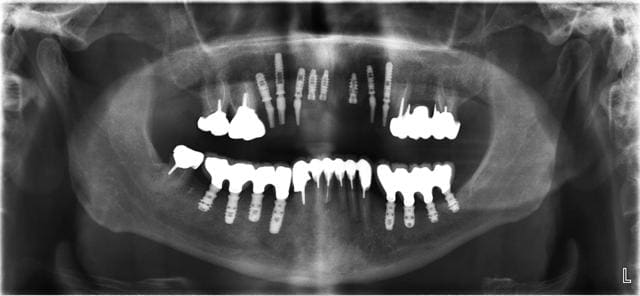

Simplement pour dire que ça peut se faire! Depuis 2 ans environ. Ok c'est au maxillaire et le bas pour l'occlusion on peut mieux faire mais chaque chose en son temps.

Moins de recul 1 an seulement pour le bas. En haut c'est une sorte de MCI avec provioire (made in drmarcus).

Maintenant si tu penses que la largeur va tu peux te baser sur cet exemple.